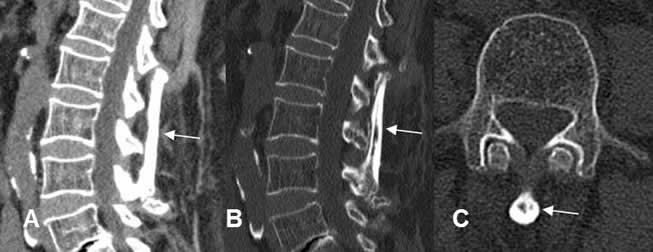

Fig 107. Injerto óseo.

A y B: TAC reconstrucción sagital y C: TAC axial. Fijación posterior con un fragmento del peroné, sobre los elementos posteriores de L2-L3 y L4.